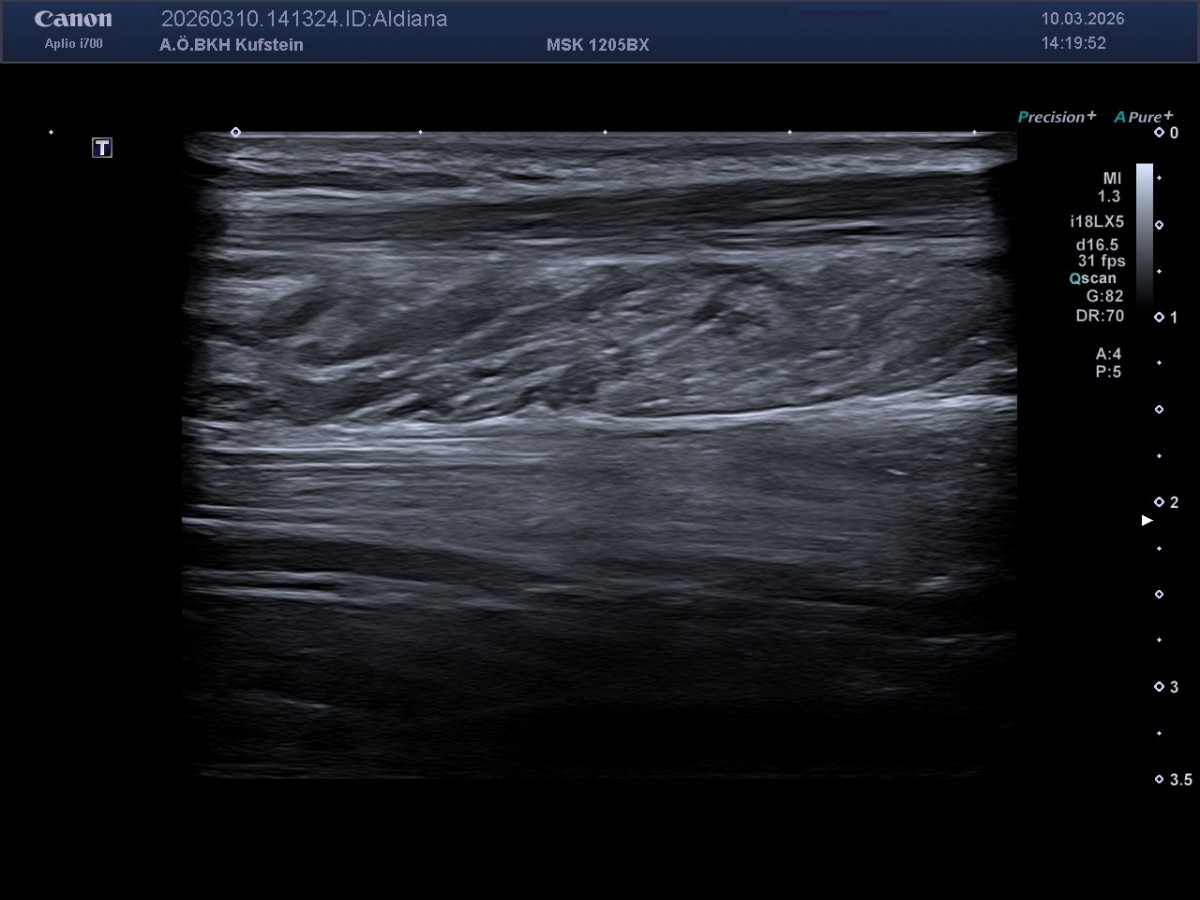

Die MedETeCh Gruppe der diesjährigen siebten Klassen besuchte am 10. März 2026 mit Frau Prof. Mag. Enthofer und Herr Prof. Mag. Dr. Zwicknagl die Abteilung für Radiologie im Krankenhaus Kufstein, um ihr medizinisches Wissen in der Praxis auszutesten. Oberarzt Dr. Martin Neururer, Radiologie-Technologe BSC Robert Nußbaumer und Dr. Paul Peyrer hießen die Schüler*innen in der Radiologie willkommen und unterstützten sie bei ihren ersten Ultraschallversuchen. Nieren, Leber, Milz, Herz, Carotis und Achillessehne konnten von den Schüler*innen eigenständig lokalisiert und anschließend auf dem Bildschirm sichtbar gemacht werden. Die Schüler*innen bedanken sich herzlich beim Team des BKH Kufstein für die freundliche und kompetente Betreuung und die Möglichkeit, selbst aktiv zu werden.